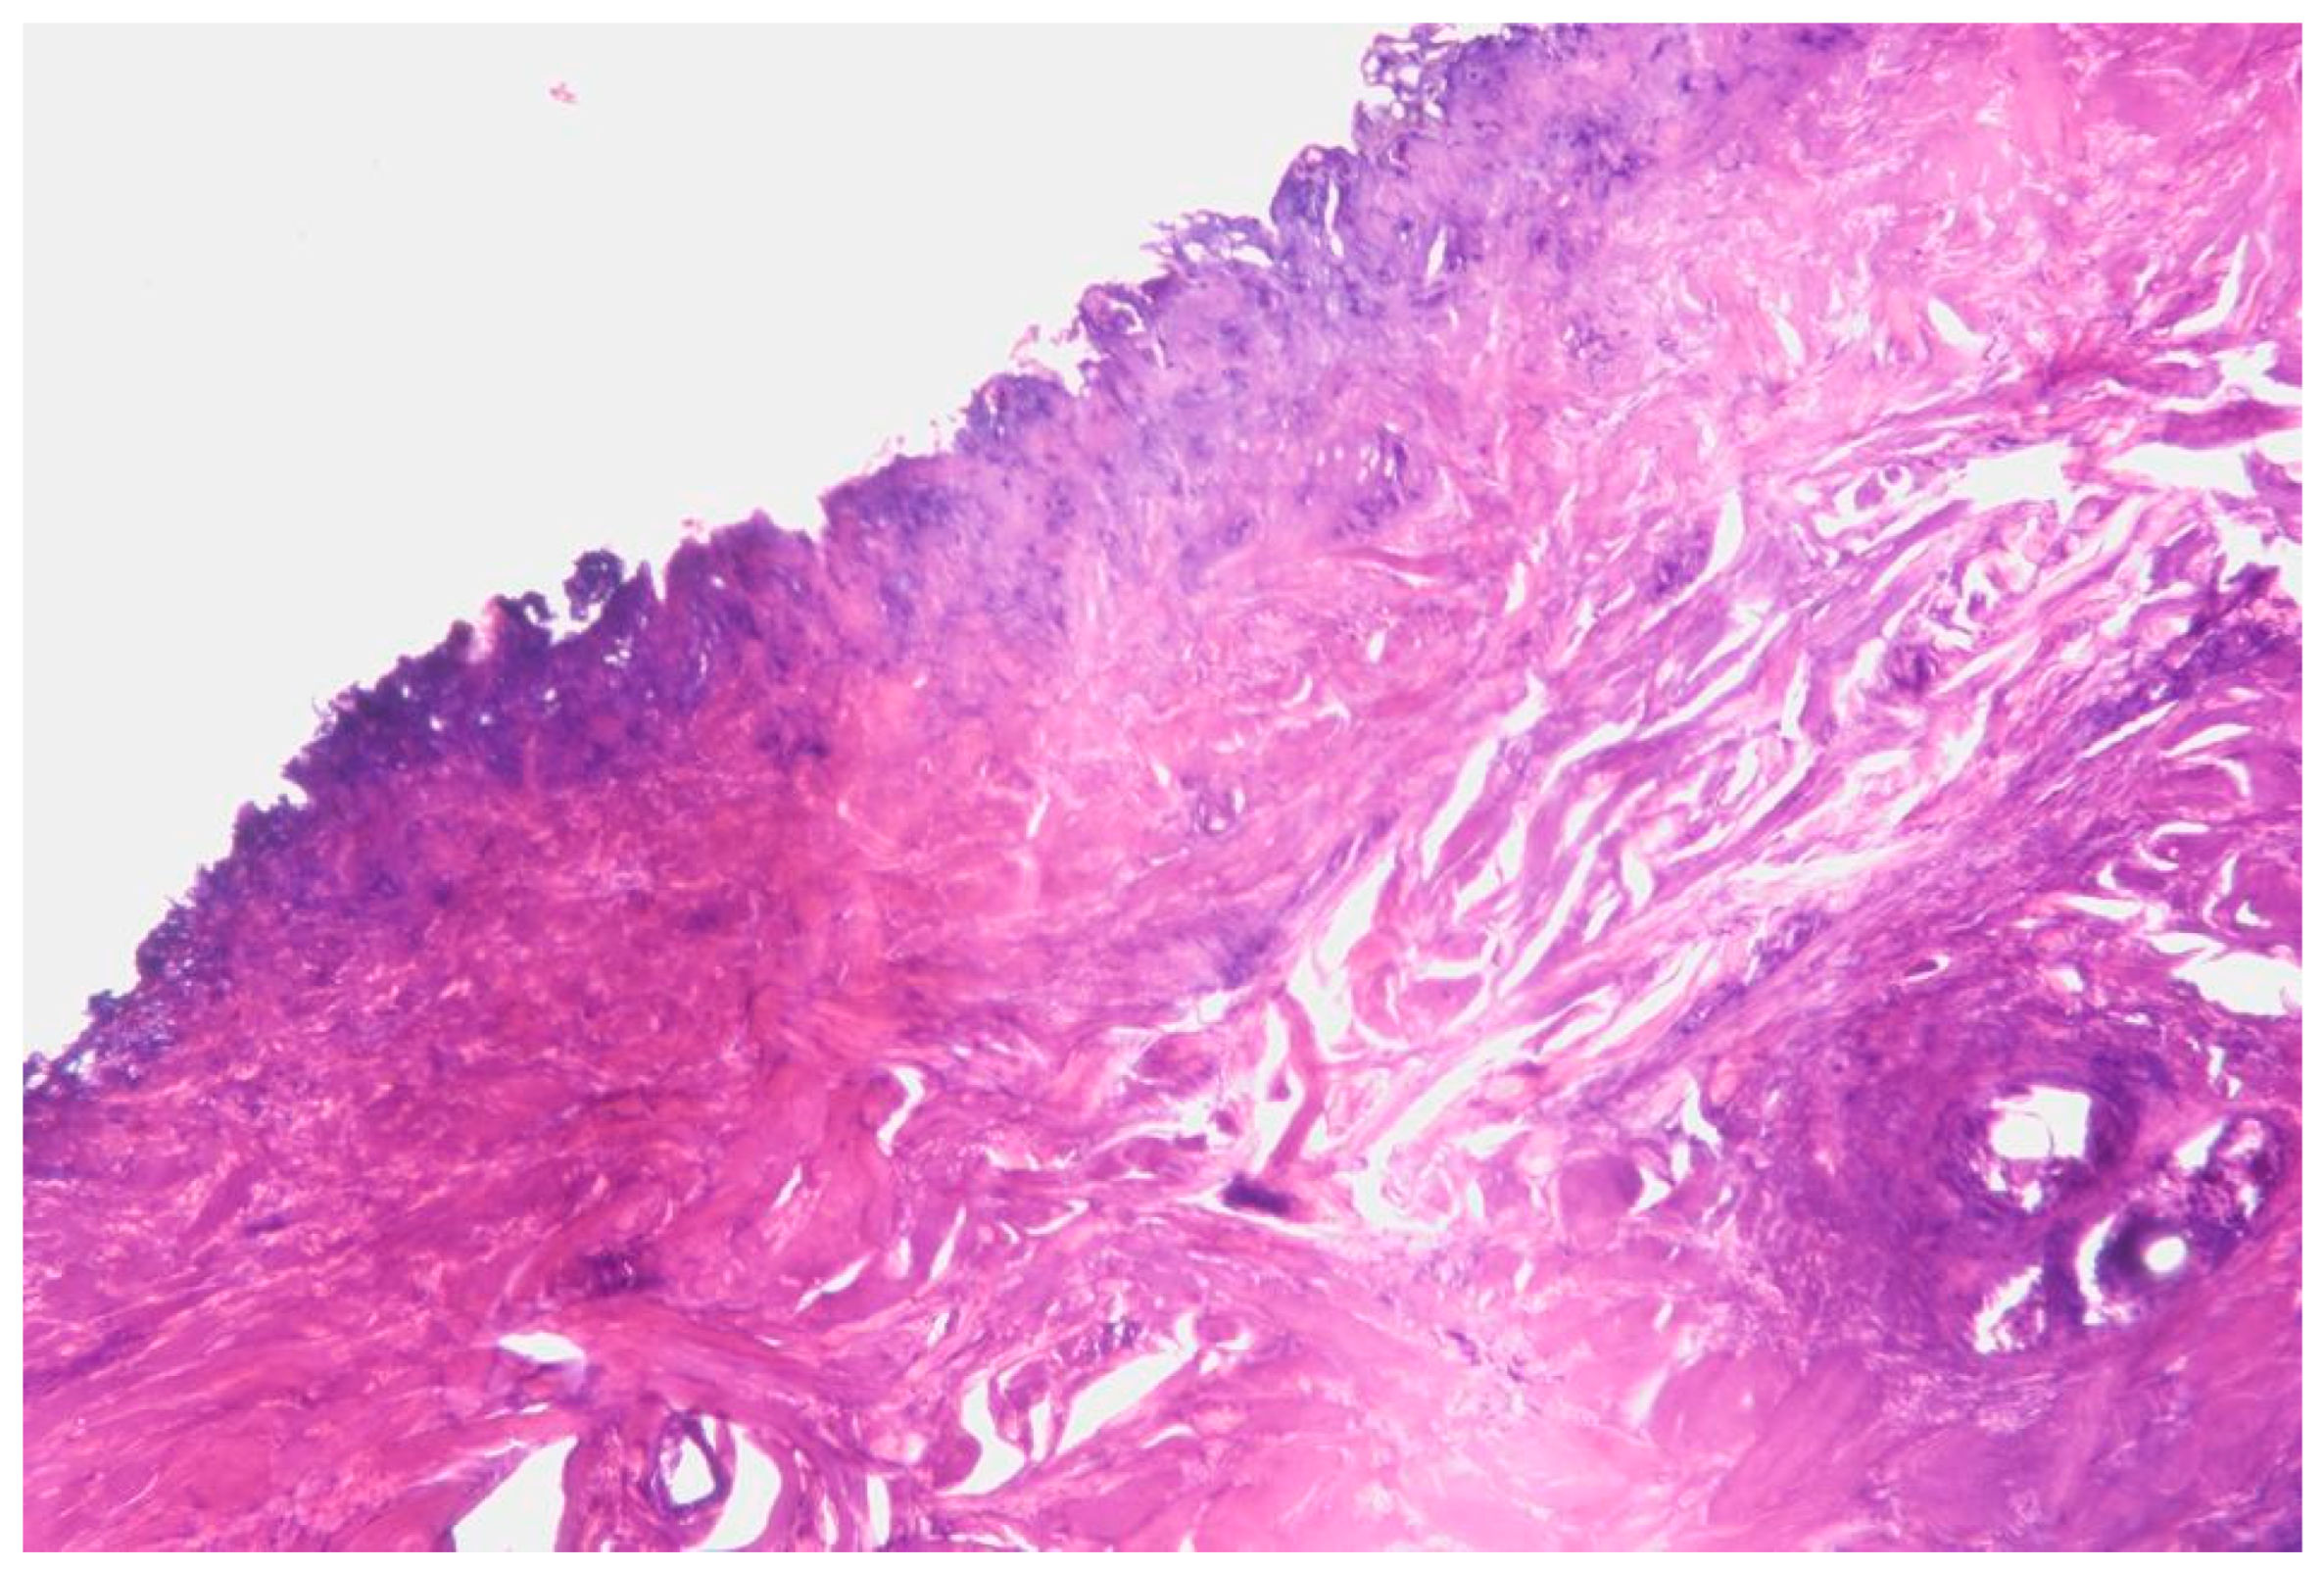

3.1.4. Clinical Case 4: Skin Dissection Area, Scalpel Incision (See Figure 5)

Description: No necrotic changes were noted, the vessels were dilated and congested, and there were extensive hemorrhages at the resection margins.

Figure 5. Skin changes following scalpel incision. H&E staining, 10× objective magnification.